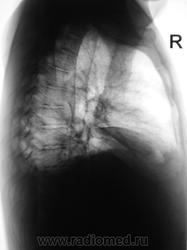

Динамика через 3 дня.

За три дня, следовательно, 0,5 л жидкости слева ушло.....а справа резко прибыло ...как будто только диафрагмы, но без значительного прибавления жидкости...Интересно....печень же за три дня так не увеличиться...

Поскольку такой внезапный парез диафрагмы маловероятен...смею предположить наличие базального плеврита справа...он же - диафрагмальный плеврит. Здорово бы было посмотреть на УЗИ - за три секунды решили бы проблему.